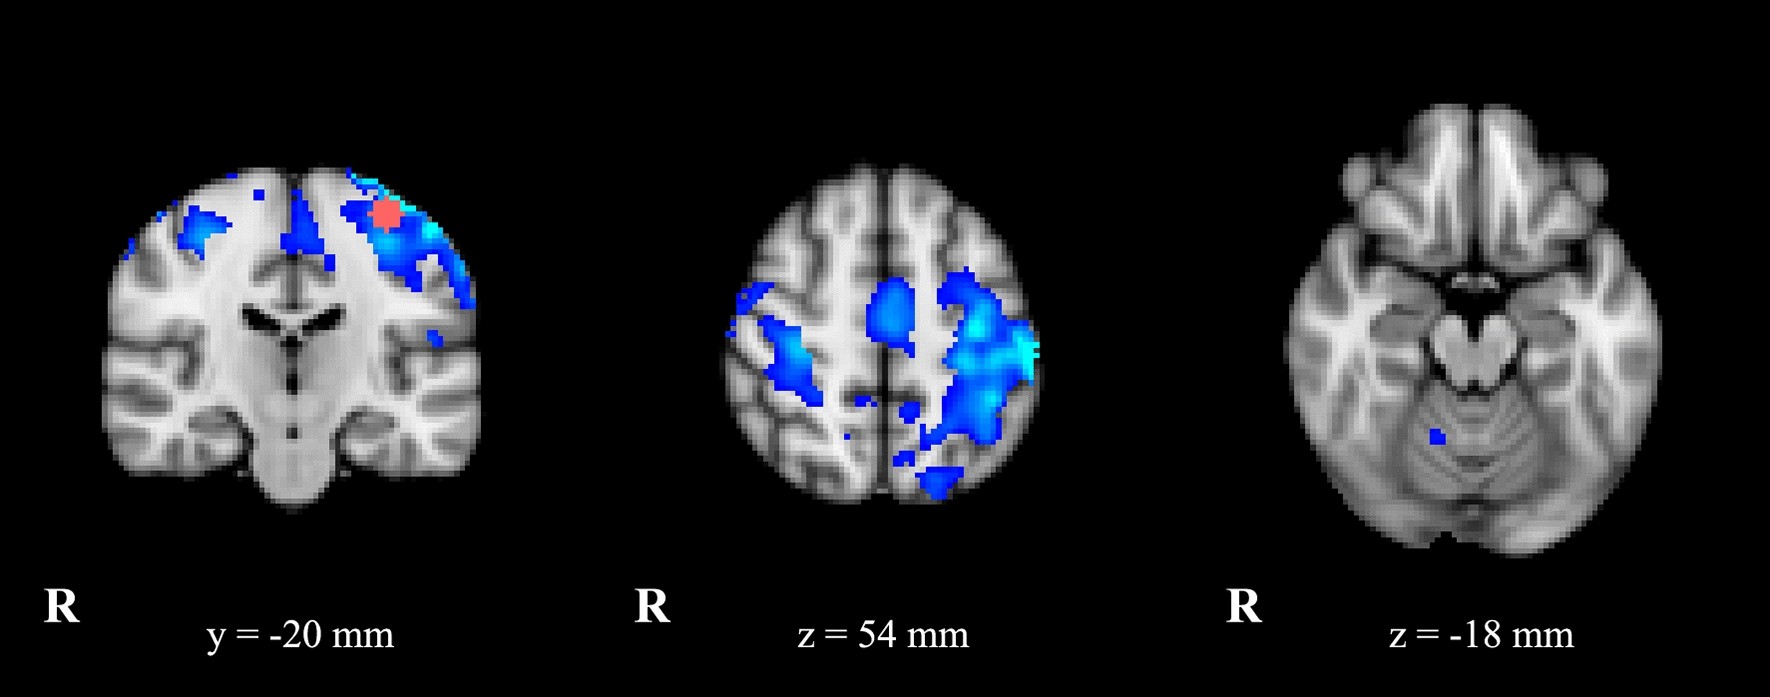

Figure 1

Statistical comparison maps between ET patients and HC for left M1-seed (ROI seed in pink). FC analysis showed a reduced connectivity (in blue) of left M1 with premotor cortex, SMA, somatosensory areas and cerebellum in patients compared to controls. Results are superimposed on axial and coronal slices of standard MNI template (Z threshold > 3.3, cluster p significance < 0.007).